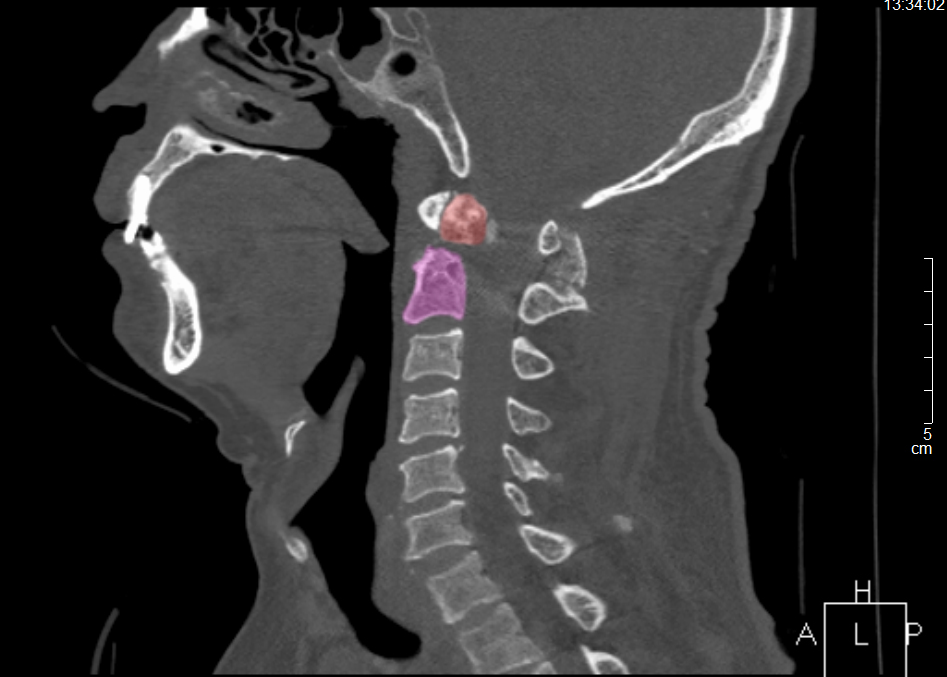

張奶奶術前CT

老人手術指征明確,但樞椎區域骨折手術本就風險較大,加之患者高齡且長期臥床,易出現肺部感染、骨質流失更多不愈合等嚴重并發癥,對醫護人員的手術技術和圍手術期管理能力要求極高。

醫護團隊根據患者病情,制定了詳細的診療方案及手術風險預案,與患者和家屬充分溝通后,為張奶奶行頸后入路寰樞椎復位內固定術,手術過程順利。